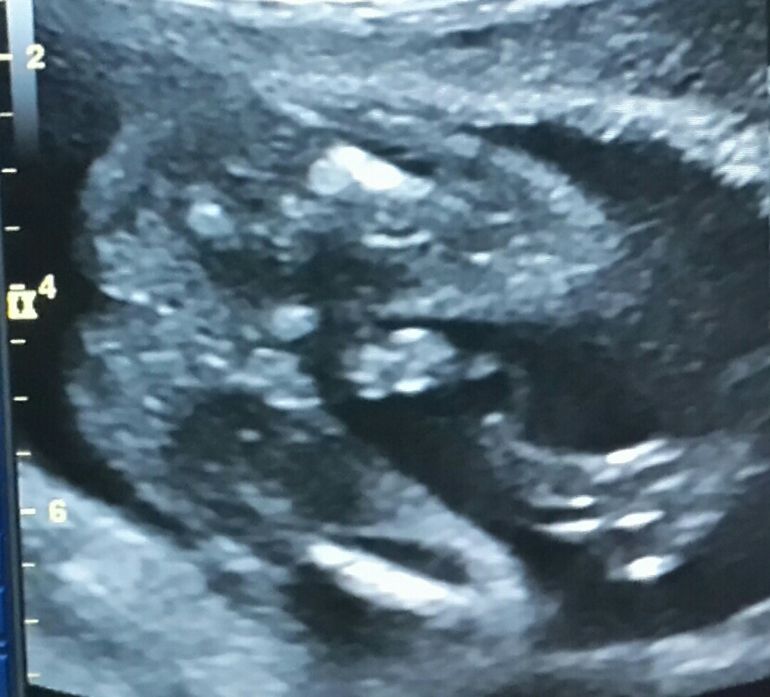

Весит сын 372гр 💪 На УЗИ в ЖК, конечно, я не получила массу положительных эмоций от увиденного, так как почти все УЗИ я только и делала, что выворачивала голову в надежде что-то понять на экране 😂 Теперь хочу на платное 3д УЗИ, чтоб увидеть ВСЕ! 😉😊

А вот, собственно, наше "все" :

П.с.: круглая мясистая попка и "то самое", что именуется бубенцами и "ооо, ни с чем не перепутаешь, точно мальчик" 😂